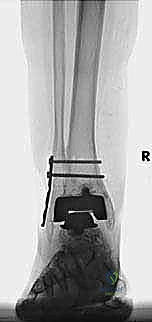

مراجعة مفصل الكاحل الصناعي هي إجراء جراحي ضروري لمعالجة المشاكل التي قد تنشأ بعد الجراحة الأولية، مثل كسور الكعبين أو عدم استقرار المفصل. يتضمن العلاج التشخيص الدقيق عبر الأشعة السينية والتصوير المقطعي، يليه التدخل الجراحي لتثبيت الكسور واستعادة وظيفة الكاحل، مع التركيز على التعافي المبكر.

تُعد جراحة مراجعة مفصل الكاحل الصناعي (Revision Total Ankle Replacement) من الإجراءات الجراحية المتقدمة والبالغة الدقة في عالم جراحة العظام الحديثة. لا تقتصر هذه الجراحة على مجرد استبدال مفصل تالف بآخر جديد، بل هي عملية إنقاذ معقدة للغاية تهدف إلى معالجة المشاكل الميكانيكية والبيولوجية التي تنشأ بعد الجراحة الأولية. من أبرز هذه المشاكل: الفشل الميكانيكي للمفصل، تحلل العظام (Osteolysis)، أو حدوث كسور معقدة في الكعبين (Malleolar Fractures) المحيطة بالمفصل الصناعي. يتطلب هذا الإجراء تقييماً سريرياً وشعاعياً دقيقاً يشمل التصوير المقطعي ثلاثي الأبعاد والأشعة السينية، يليه تدخل جراحي دقيق لاستعادة التوازن الحيوي والميكانيكي للكاحل والحفاظ على الطرف من البتر أو الدمج.

- الأشعة السينية مع تحميل الوزن (Weight-bearing X-rays): لتقييم الزوايا الميكانيكية وتحديد مدى هبوط المفصل أو وجود كسور في الكعب.

كسور الكعبين (Malleolar Fractures) المصاحبة للمفصل الصناعي

من أعقد التحديات التي تواجه جراحي العظام هي حدوث كسور في الكعب الداخلي (Medial Malleolus) أو الخارجي (Lateral Malleolus) في وجود مفصل صناعي. تحدث هذه الكسور لعدة أسباب:

علاج هذه الكسور يتطلب مهارة فائقة من الدكتور محمد هطيف، حيث يتم استخدام تقنيات الجراحة الميكروسكوبية وتثبيت الكسور باستخدام صفائح معدنية دقيقة ومسامير (Locking Plates) دون المساس بثبات المفصل الصناعي، أو يتم دمج علاج الكسر ضمن عملية مراجعة المفصل الكلية إذا كان المفصل نفسه تالفاً.

يتم إدخال المفصل الجديد المخصص للمراجعة، والذي يحتوي غالباً على سيقان (Stems) تدخل عميقاً في عظمة الساق وعظمة الكاحل لضمان الثبات الميكانيكي. في حال وجود كسور في الكعب، يتم تثبيتها في هذه المرحلة.